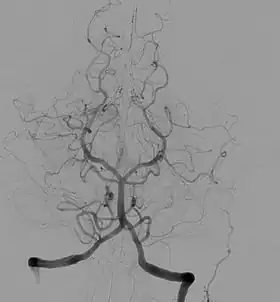

Angiography is the use of fluoroscopy to view the cardiovascular system. An iodine-based contrast is injected into the bloodstream and watched as it travels around. Since liquid blood and the vessels are not very dense, a contrast with high density (like the large iodine atoms) is used to view the vessels under X-ray. Angiography is used to find aneurysms, leaks, blockages (thromboses), new vessel growth, and placement of catheters and stents. Balloon angioplasty is often done with angiography.